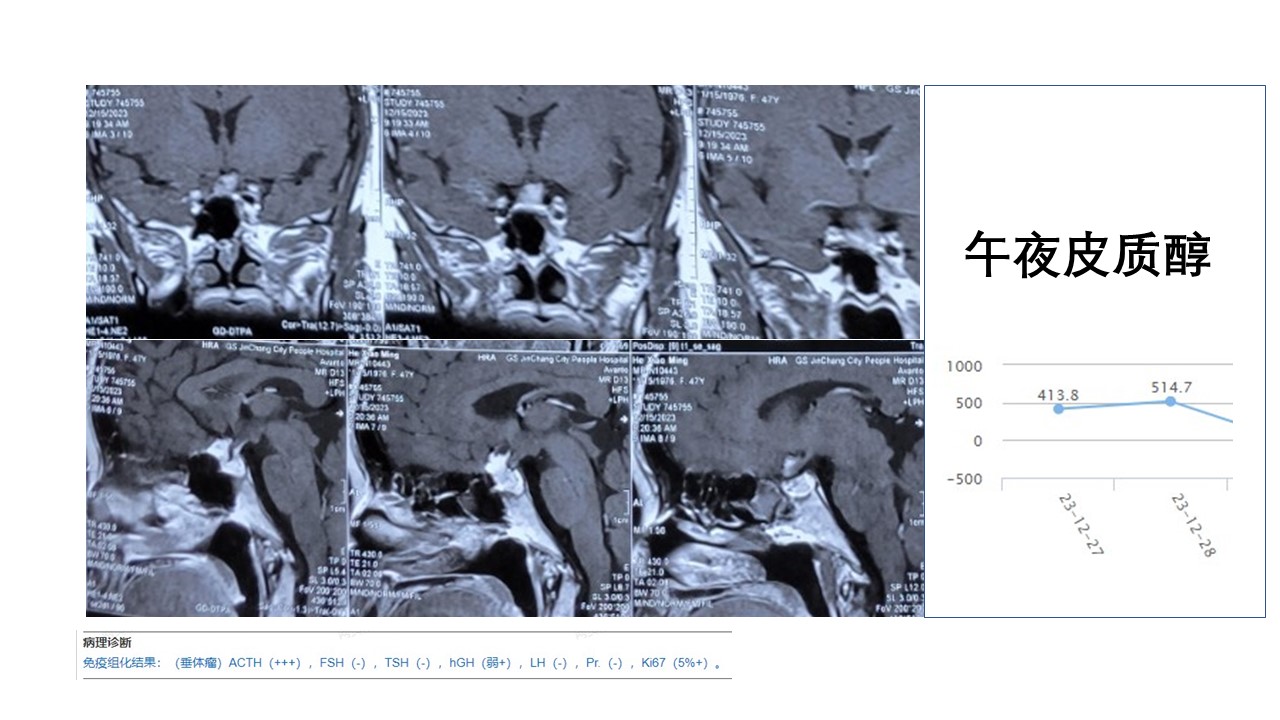

神经内镜经鼻扩大入路切除复发垂体神经内分泌肿瘤

术后病理和患者情况,无脑脊液漏,面容逐步恢复正常